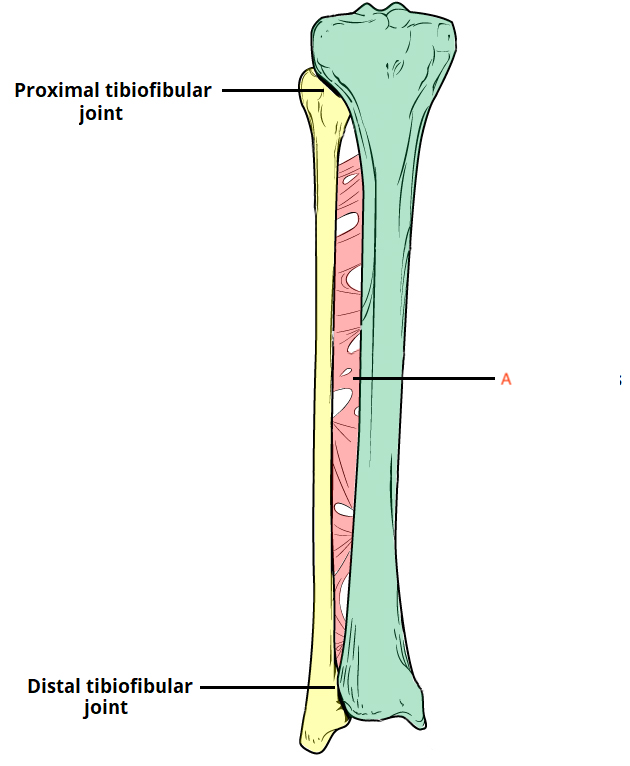

what type of joint is A?

symphysis

syndesmosis

synostosis

synchondrosis

gomphosis

what type of joint is A?

symphysis

syndesmosis

synostosis

synchondrosis

gomphosis

what is a synostosis fibrous joint? [1]

whats a bone with an example of a synostosis joint? [1]

what is a syndemosis fibrous joint? [1]

whats a bone with an example of where find a syndemosis joint? [1]

what is a gomphosis fibrous joint? [1]

whats a bone with an example of where find a gomphosis joint? [1]

what is a synostosis fibrous joint? [1]

At some sutures, the connective tissue will ossify and be converted into bone, causing the adjacent bones to fuse to each other (and make one big bone)

whats a bone with an example of a synostosis joint? [1]

frontal bone

what is a syndemosis fibrous joint? [1]

sheet of fibrous tissue between bones = interosseous membrane

whats a bone with an example of where find a syndemosis joint? [1]

between radius and ulnar / between tibia and fibula

what is a gomphosis fibrous joint? [1]

cone shaped peg fits into a socket

whats a bone with an example of where find a gomphosis joint? [1]

teeth